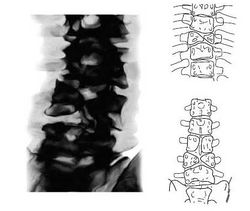

Существуют четкие критерии определения биологического возраста по рентгенограммам позвоночника. При этом в различных возрастных диапазонах анализируют форму позвонков, состояние замыкательных пластин, просвет сосудистого канала в телах позвонков, физиологические изгибы позвоночника, состояние краевых кантов - лимбусов (Камалов И.И., 1992). Однако, учитывая, что скелет каждого отдельно взятого ребенка развивается в течение его жизни относительно равномерно, для определения костного возраста целесообразнее проводить рентгенологическое исследование не позвоночника, а лучезапястного сустава и кисти.

Общая схема возрастных особенностей лучезапястного сустава и кисти представлена на рис.